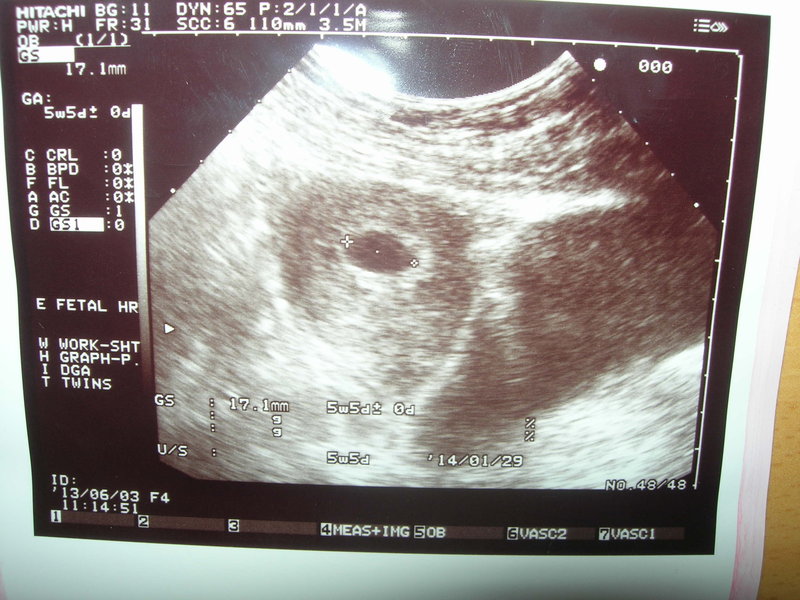

可以請有經驗的媽咪幫我看一下嗎~懷孕六週左右的超音波照片

醫生照完超音波後,根據胚囊大小推估約5週5天,1.71cm大小

想請教有經驗的媽媽,約六週的胚囊就是像圖示一樣,黑黑一個圓圈嗎

因為我以為要可以看到某個東西或什麼的,而不是黑黑的都沒東西

要多大週數才可以看到胚囊裡有東西呢